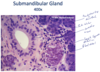

Submandibular Gland

* Both serous and mucous cells.

* Serous cells form serous demilune capping mucous acini.

* Myoepithelial cells surround acini.